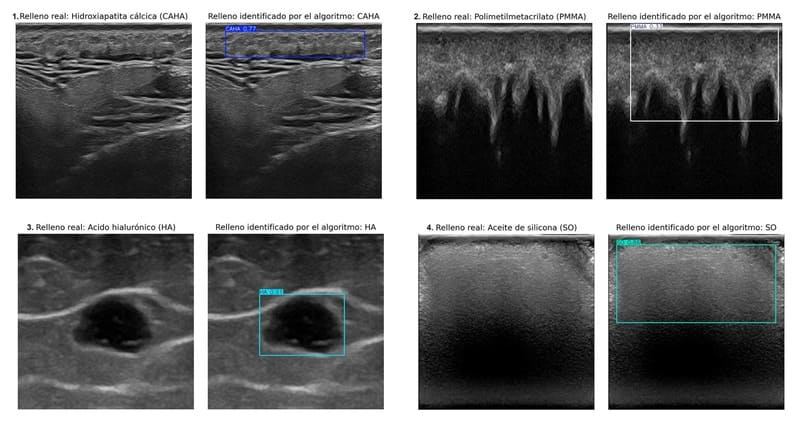

Imágenes de la investigación. Universidad de Granada

El equipo de investigación dirigido por la doctora Ximena Worstman de la Universidad de Chile, que ha contado con la decisiva participación de los profesores del Departamento de Ciencias de la Computación e Inteligencia Artificial de la Universidad de Granada Manuel Lozano y Francisco J. Rodríguez, ha creado un sistema de inteligencia artificial basado en aprendizaje profundo. Este algoritmo es capaz de identificar y discriminar automáticamente, en imágenes ecográficas, cuatro tipos de rellenos cosméticos: hidroxiapatita cálcica, ácido hialurónico, polimetilmetacrilatoy aceite de silicona.